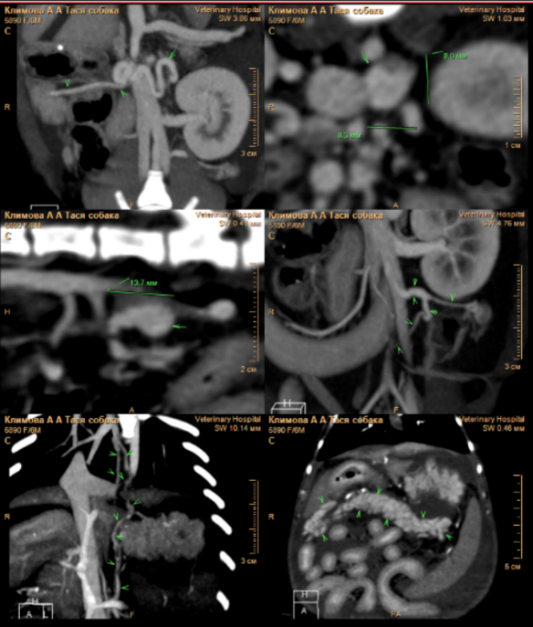

По результатам КТ-ангиографии выявлены следующие изменения (фото 2):

- множественные портокавальные анастомозы, предположительно, приобретенного характера;

- микрогепатия и отек стенки желчного пузыря;

- отек паренхимы поджелудочной железы;

- изменения в стенках желудка и тонкого кишечника, вероятно, обусловленные венозным застоем или воспалительными процессами;

- наличие асцита.